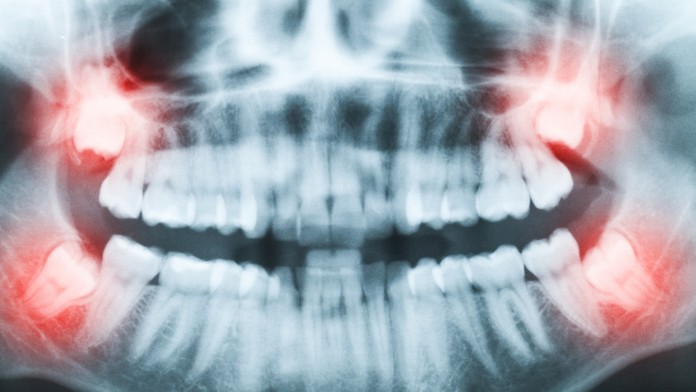

Vedci zistili, prečo nám zuby múdrosti rastú až na prahu dospelosti

Ilustračná snímka.

Zdroj: shutterstock/DeymosHR

U Homo sapiens dorastajú posledné stoličky - zuby múdrosti, niekedy až pred 20. rokom života. Prečo je to tak, je premetom dlhodobého výskumu, ktorý teraz priniesol prvé výsledky. Na túto otázku čiastočne odpovedali vedci z University of Arizona, píše portál Science Alert.

Jedným z najdôležitejších faktorov, ktoré predurčujú vývoj chrupu, je dostatok miesta a v tomto smere je ľudská lebka nedokonalá. Nedostatok miesta pre poslednýu sadu stoličiek tkzv. Zubov múdrosti, môže byť zdrojom vážnych zdravotných problémov. To, že nám zuby múdrosti rastú tak neskoro, však problém nedostatkom miesta vysvetľuje iba čiastočne.